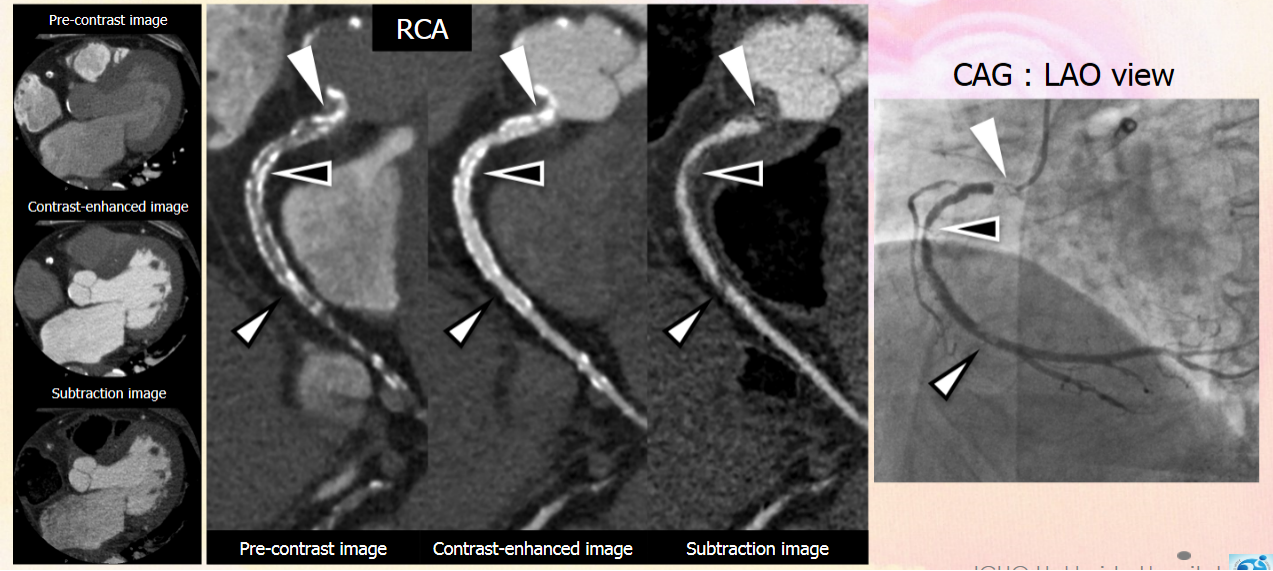

病例四 PCI后復(fù)查,前降支支架內(nèi)再狹窄。

冠脈減影前 冠脈減影后

病例五 高鈣化積分冠脈檢查

心血管方面 佳能640層鐠黃金CT依托0.275秒的掃描速度、16厘米的全器官覆蓋,旋轉(zhuǎn)1圈即可實(shí)現(xiàn)心臟成像,徹底解決了心律不齊、房顫等檢查禁忌,從而根除了錯(cuò)層偽影。同時(shí)掃描劑量大大降低,僅僅相當(dāng)于64排CT的二十分之一,自然本底輻射的八分之一。對(duì)于患有肺心病或患心臟病同時(shí)伴有呼吸系統(tǒng)疾病的病人,即使在不屏氣的情況下,也能獲得高質(zhì)量的心臟圖像。此外還可以對(duì)狹窄斑塊成分進(jìn)行分析,有效預(yù)防急性心肌梗死的發(fā)生,大大降低隱匿性冠心病的致死風(fēng)險(xiǎn)。獨(dú)有的智能冠脈減影技術(shù),可實(shí)現(xiàn)高鈣化積分病人心臟成像和PCI手術(shù)后支架病人的復(fù)查,拓展了冠脈CTA檢查的臨床領(lǐng)域。